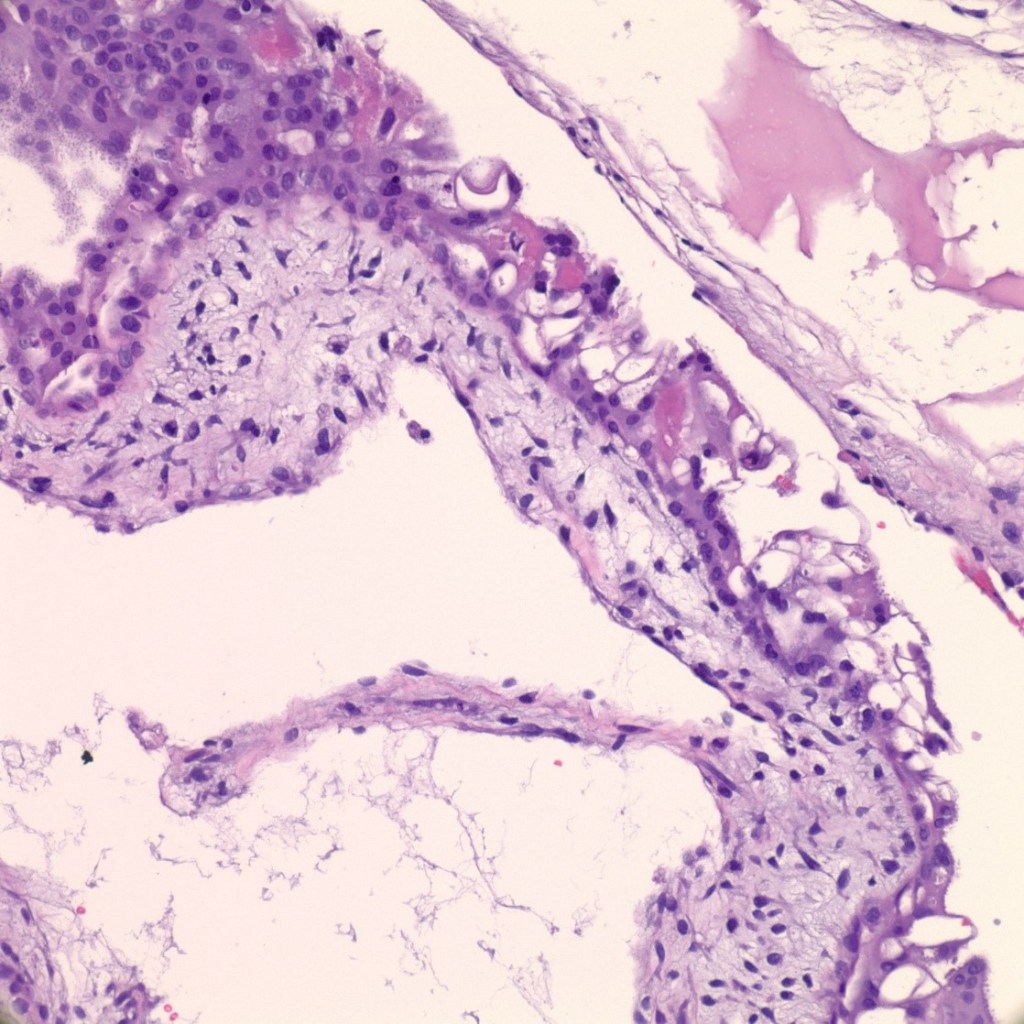

- The low-power view reveals a mix of small fibrotic villi and larger villi (figure 9).

- Some trophoblastic proliferation (in lace-like pattern) can be seen (figure 10).

- Embryo or fetus can be present.

- A limited number of cisterns are many times appreciated.

Differential diagnosis: very early complete hydatidiform mole or chromosomal abnormalities such as trisomies (figure 10).